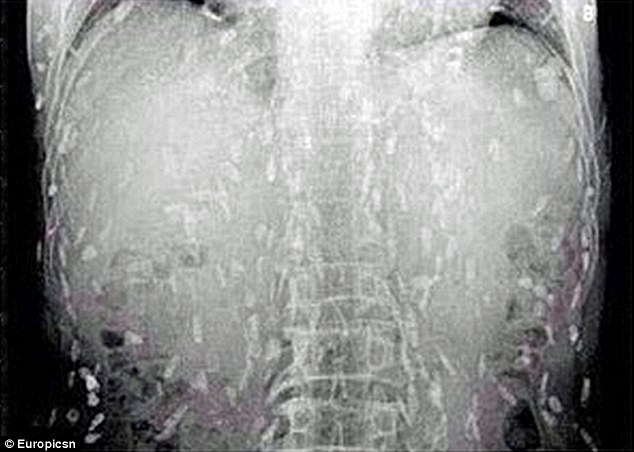

Tin tức trên Daily Mail cho biết, một người đàn ông Trung Quốc đã đến gặp bác sĩ sau khi xuất hiện các triệu chứng đau bụng và ngứa da. Sau khi kiểm tra và chụp cắt lớp, các bác sĩ phát hiện sán dây đã ký sinh trên khắp cơ thể bệnh nhân này.

Tình yêu sushi suýt chút nữa đã khiến người đàn ông Trung Quốc mất mạng do sán ký sinh khắp cơ thể. |

Nguyên nhân được cho là do ông này ăn quá nhiều món sushi và sashimi (gỏi cá). Các bác sĩ tin rằng, món ăn làm từ cá và thịt chưa nấu chín kiểu Nhật mà bệnh nhân ăn đã bị nhiễm sán.

Hiện tại, "tín đồ" sushi này đã được điều trị tại bệnh viện Nhân dân số 8 ở Quảng Châu, tỉnh Quảng Đông, miền Đông Trung Quốc.

Tiến sĩ Yin đến từ bệnh viện Nhân dân số 8 cho biết trên trang web mags.com rằng, nếu ăn những thực phẩm chưa được nấu chín bị nhiễm trứng sán dây, con người có thể mắc bệnh nang sán khi sán dây xâm nhập vào mạch máu, thậm chí có thể đe dọa tính mạng khi sán nhiễm lên não bộ.